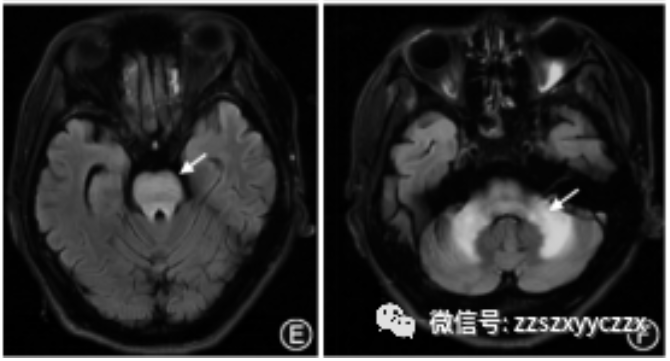

头核磁影像学检查:头MRI双侧基底节、丘脑、脑干T2序列异常信号影,DWI可见皮-髓交界区花边征的高信号影。而“花边征”也是神经元核内包涵体病(NIID)的典型影像学特征。随后又完善了NOTCH2NLC基因及皮肤活检,未发现NOTCH2NLC基因突变,病理也没有发现神经元核内包涵体。基于以上检查结果,排除了NIID的可能。

A图:头MRI双侧基底节、丘脑T2序列异常信号影,DWI可见皮-髓交界区花边征的高信号影;B图:DWI皮-髓交界区花边征的高信号影消失。

图2 肝豆状核变性患者的颅脑磁共振成像表现。T1加权像示壳核低信号(A,箭头),T2加权像示壳核和屏状核(B,箭头)、尾状核头部和丘脑(C,箭头).中脑(D,箭头)、脑桥(E,箭头)及小脑(F,箭头)高信号。患者经过治疗后,基底节区的T2高信号(G,箭头)逐渐变浅、变小(H,箭头)。